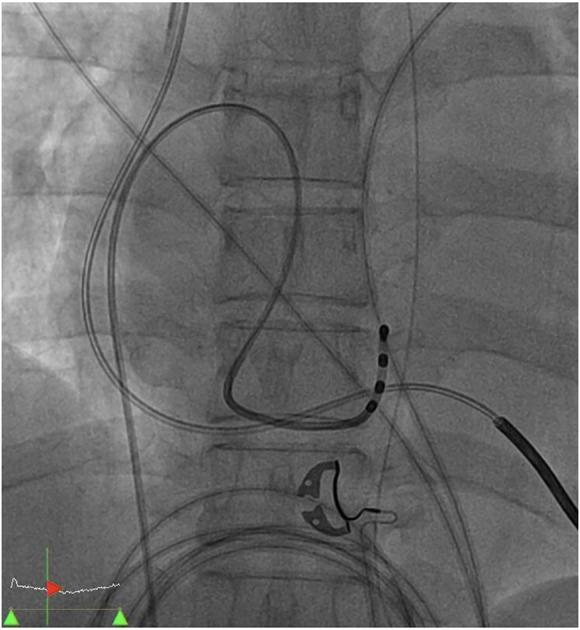

A 55-year-old woman with a history of advanced heart failure was admitted to the rehabilitation ward after a recent stroke. During hospitalization, she had paroxysmal atrial fibrillation with rapid ventricular response resulting from fluid overload. While atrial fibrillation was spontaneously reversed to sinus rhythm after diuresis, she developed multiple episodes of polymorphic ventricular tachycardia along with sinus bradycardia and prolonged QTc interval. She became hypotensive despite appropriate medical management. Pacing through her implantable cardioverter-defibrillator was attempted but worsened her hypotension. Ventricular dyssynchrony was suspected. Temporary transvenous atrial pacing through the coronary sinus was performed, which stabilized her blood pressure and improved end-organ perfusion. A permanent biventricular pacemaker was later implanted, and she was safely discharged to a nursing home.

一名55岁有晚期心力衰竭病史的女性,近期中风后入住康复病房。住院期间,因液体超负荷出现阵发性心房颤动伴快速心室反应。利尿后心房颤动自发转为窦性心律,但她出现了多次多形性室性心动过速,同时伴有窦性心动过缓和QTc间期延长。尽管进行了适当的药物治疗,她仍出现低血压。尝试通过植入式心脏复律除颤器进行起搏,但使她的低血压情况恶化。怀疑存在心室不同步。遂行经冠状静脉窦临时经静脉心房起搏,这使她的血压稳定,改善了终末器官灌注。后来植入了永久性双心室起搏器,她安全出院并入住疗养院。